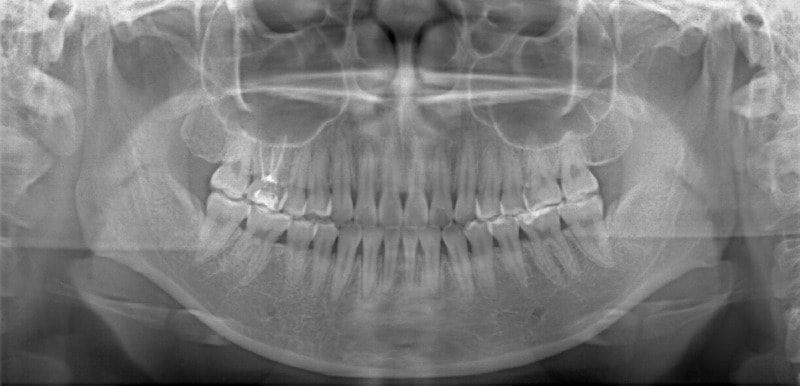

検査時レントゲンパントモ

現代人には珍しく8番(親知らず)が直立して萌出しています。